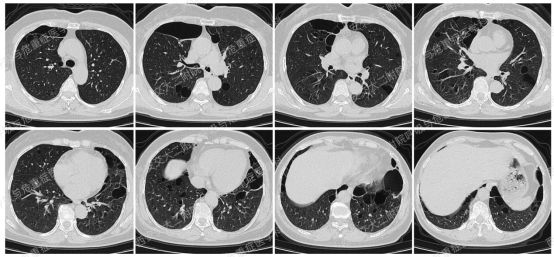

上图与Case 2比较相似,所以诊断LAM没有问题,还需进一步排查系散发型还是结节性硬化症累及。

影像学评估发现患者多系统受累(肝脏错构瘤、双肾血管平滑肌脂肪瘤、颅脑多发异常信号结节)。追问病史,患者本人无皮疹、癫痫及智力低下;患者儿子有面部皮脂腺瘤,无癫痫及智力低下,胸腹部CT未见异常,皮肤科已确诊结节性硬化症;患者女儿面容及智力均正常;建议患者进一步行TSC基因检测,结果回报TSC2突变,结节性硬化症诊断明确。

患者尝试口服西罗莫司2mg/日,消化道难以耐受,减至1mg/日,仍有恶心等不适,自行停药,不愿再尝试药物治疗,目前随访观察中。